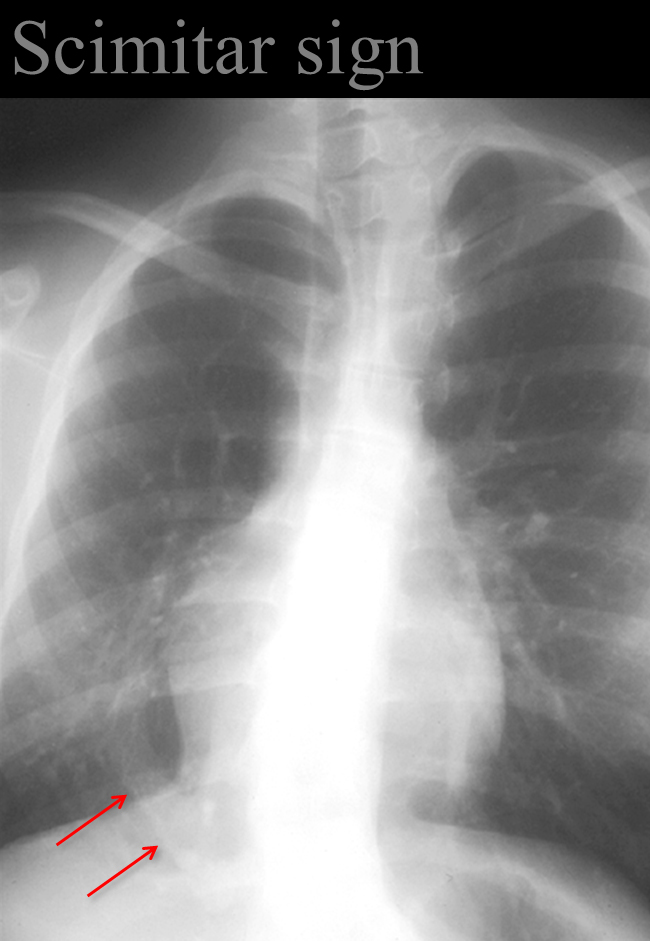

Gallery Signs Scimitar sign Anomalous venus return below the diaphragm (hypoplastic Rt lung/venolobar syndrome)

Anomalous venus return below the diaphragm

(hypoplastic Rt lung/venolobar syndrome)